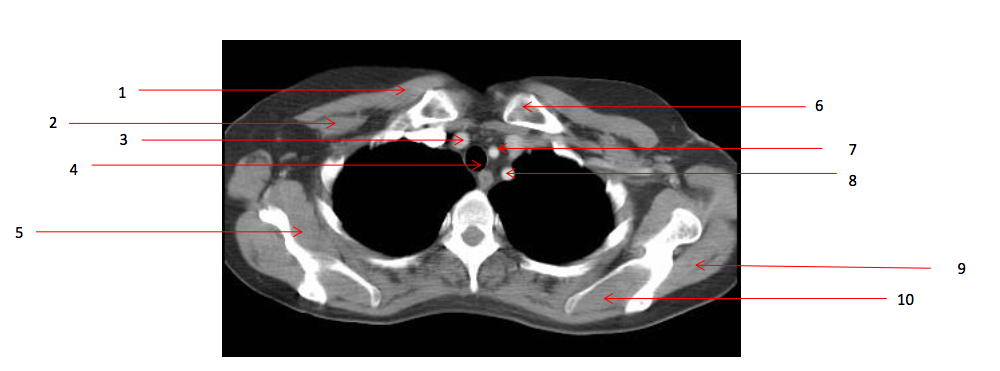

Number 19?

Arch of aorta

Number 23?

Pulmonary trunk

Number 17?

SVC

Number 20?

Ascending aorta

Number 18?

trachea

Q

Number 22?